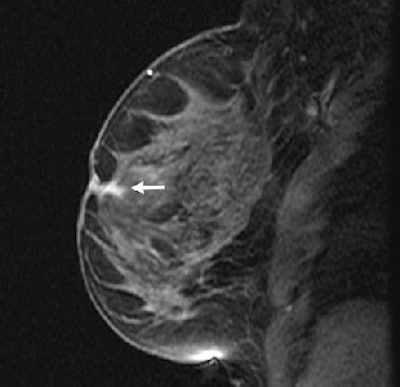

| Fifty-four-year-old woman with history of left breast cancer with normal mammogram and no palpable lumps, in whom MRI detected speculated right breast mass with no sonographic correlate. Sagittal fat-suppressed T1-weighted, contrast-enhanced scout image from MRI-guided biopsy shows 0.9 cm mass with speculated borders, irregular shape, and heterogeneous enhancement in right retroareolar region (arrow). |

| Same patient as above. Sagittal fat-suppressed T1-weighted, contrast-enhanced MRI on date of MRI-guided needle localization shows persistence of right retroareolar speculated mass (arrow). MRI-guided needle localization yielded 0.5 cm infiltration ductal carcinoma and ductal carcinoma in-situ. Liberman L, Bracero N, Morris E, Thornton C, Dershaw DD, "MRI-Guided 9-Gauge Vacuum-Assisted Breast Biopsy: Initial Clinical Experience" (AJR 2005;185:183-193). |